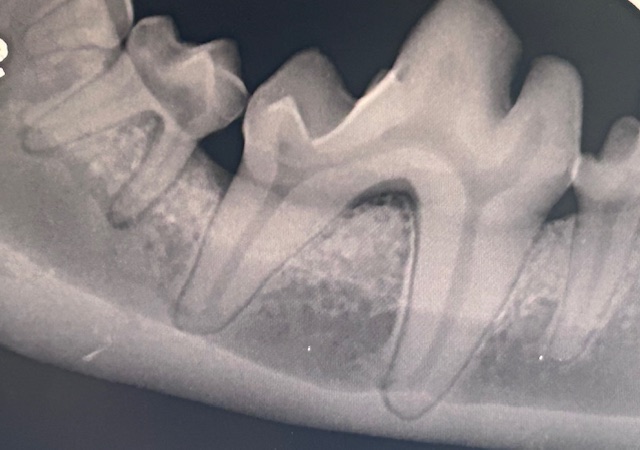

Dental radiography

Integrating Dental Radiography in COHAT procedures

Understand what constitutes a diagnostic radiograph, interpretation, appropriate record keeping, improving work flow